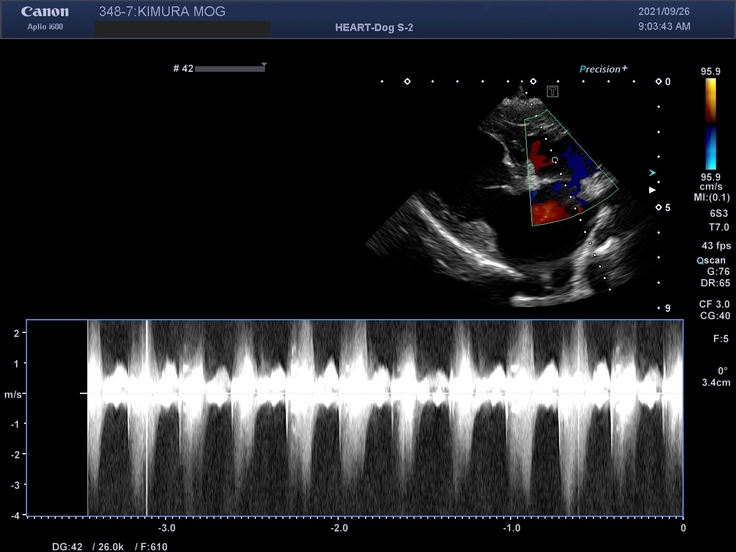

獣医の診断結果は「末期の僧帽弁閉鎖不全症」

心臓の弁が正常に動かず、心臓内で血液が逆流してしまう心臓病です。

これにより、血液が心臓に溜まってしまい、心臓が肥大化します。

末期になると肥大化した心臓が肺の血管を圧迫し、肺に水が溜まる「肺水腫」を引き起こします。

▼治療の進捗

現在、投薬治療を中心に進めております。

皆さんに安心してご支援いただける様、以下に診断書等を添付させていただきます。

投薬治療を続けているものの、容体は悪くなっていく一方です。

投薬はあくまで症状を抑えるのみなので、回復するにはやはり手術しかありません。